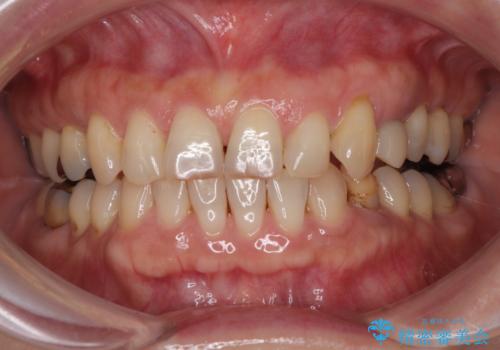

最新の症例

Latest cases